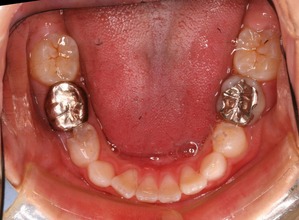

現在の状況です

中学2年生になりました。

上顎も下顎もそこそこの歯列になっていると思います。

咬み合わせも良好です

なんと、大人の歯は虫歯0本で管理されてます!

こういった部分は歯列矯正の技術的な部分はまったくなく、知識という部分をふんだんに応用した結果です。

すくなくとも、このような治療例(歯列矯正治療費は一切いただいておりません。観察料金も0円です)